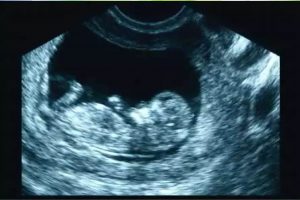

Diplomados en Ultrasonografía